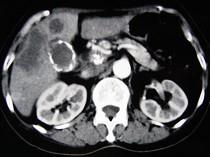

问题 女,66岁,右上腹痛,发热伴有黄疸两月余,消瘦、纳差,影像检查如图,最可能的诊断是()

选项 A.胆囊结石及脂肪肝 B.胆囊结石及肝血管瘤 C.胆囊癌肝转移 D.肝内胆管细胞癌 E.胆囊癌及原发性肝癌

答案 C